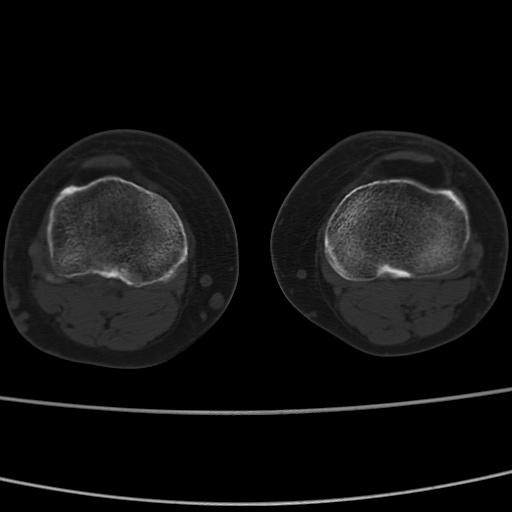

女性,50岁。【请提供患者临床症状体征】

右膝关节退行性改变,关节游离鼠。

右膝关节退行性改变,滑膜黏液囊钙/骨化并游离。

右膝关节退行性改变